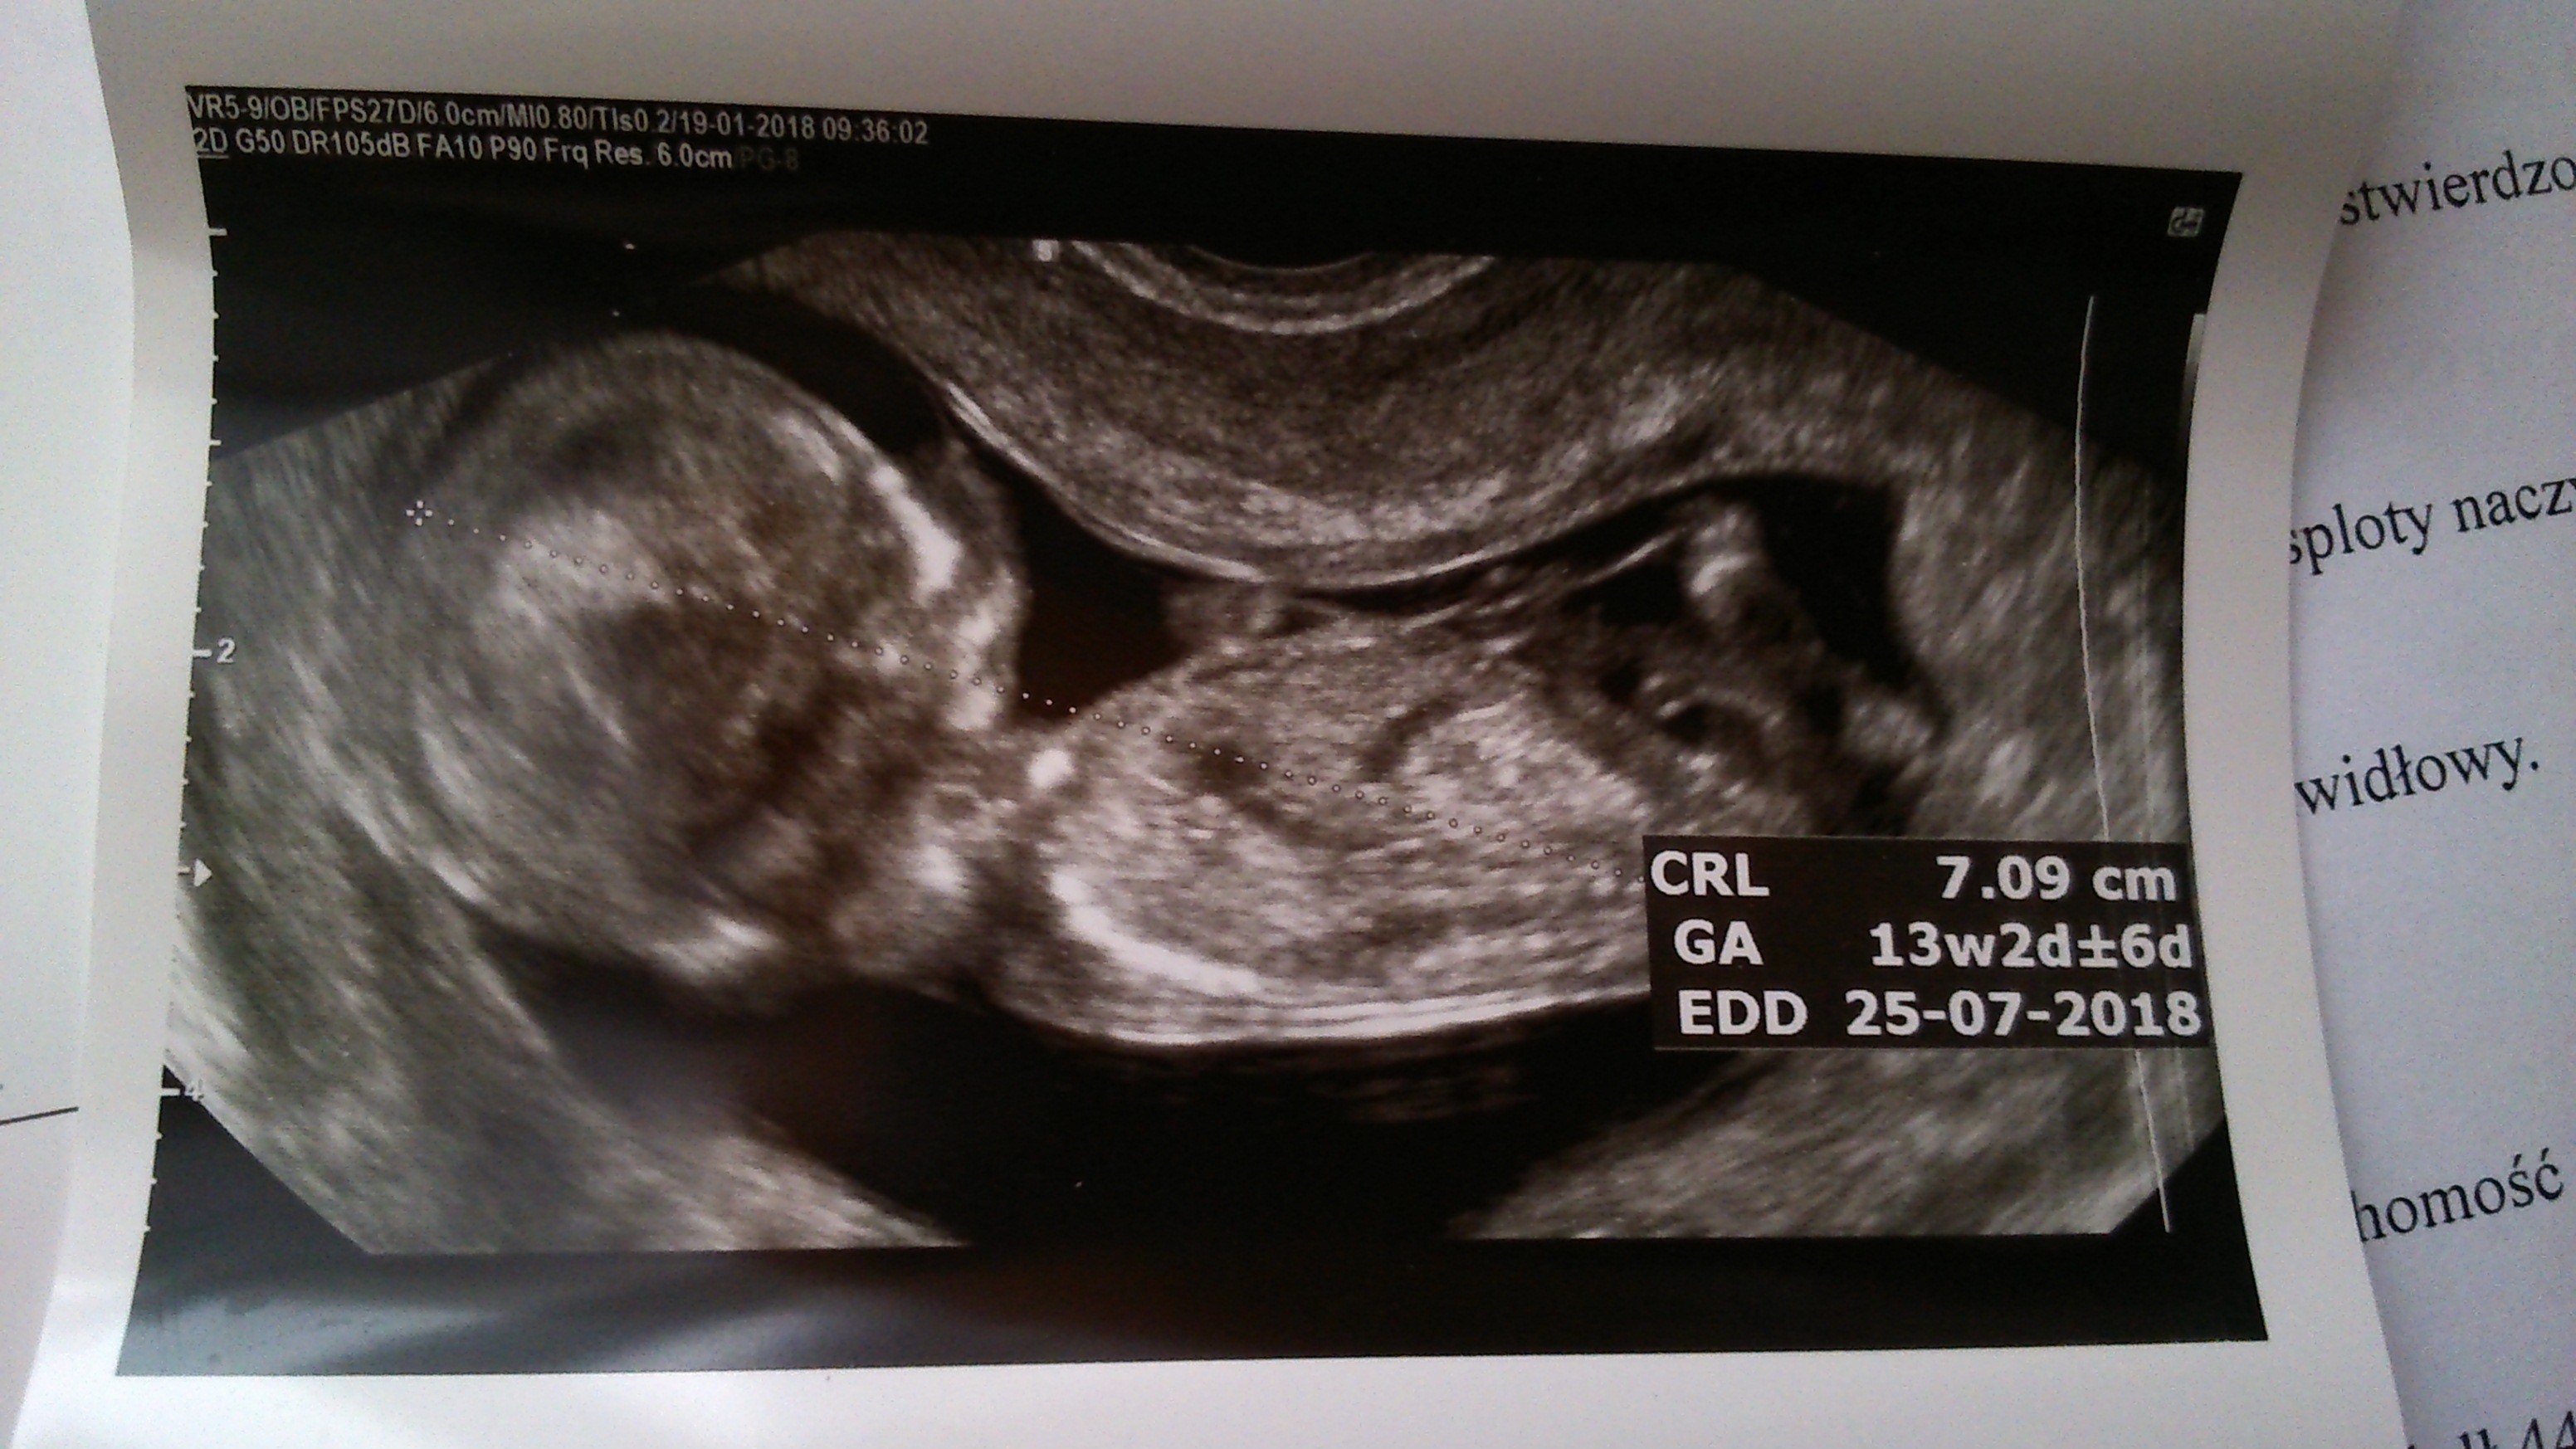

Zobacz załącznik 835942 Zobacz załącznik 835943 Zobacz załącznik 835945 Ja juz po wizycie. Wszystko w porządku jest. Dzidzia strasznie się wierciła. Ale niestety nie chciała się pokazać więc na poznanie płci musze poczekać do 8 marca na usg polowkowe. Maluszek ma już 7 cm. Serduszko 140 ud/min, NT 1,4 mm,

bobas był w super humorze tak się uśmiechał aż buzia otwarta :-)wg usg dzidzia starsza i termin przesunął się na 25 lipiec :-)usg miałam robione przez to i przez to :-D